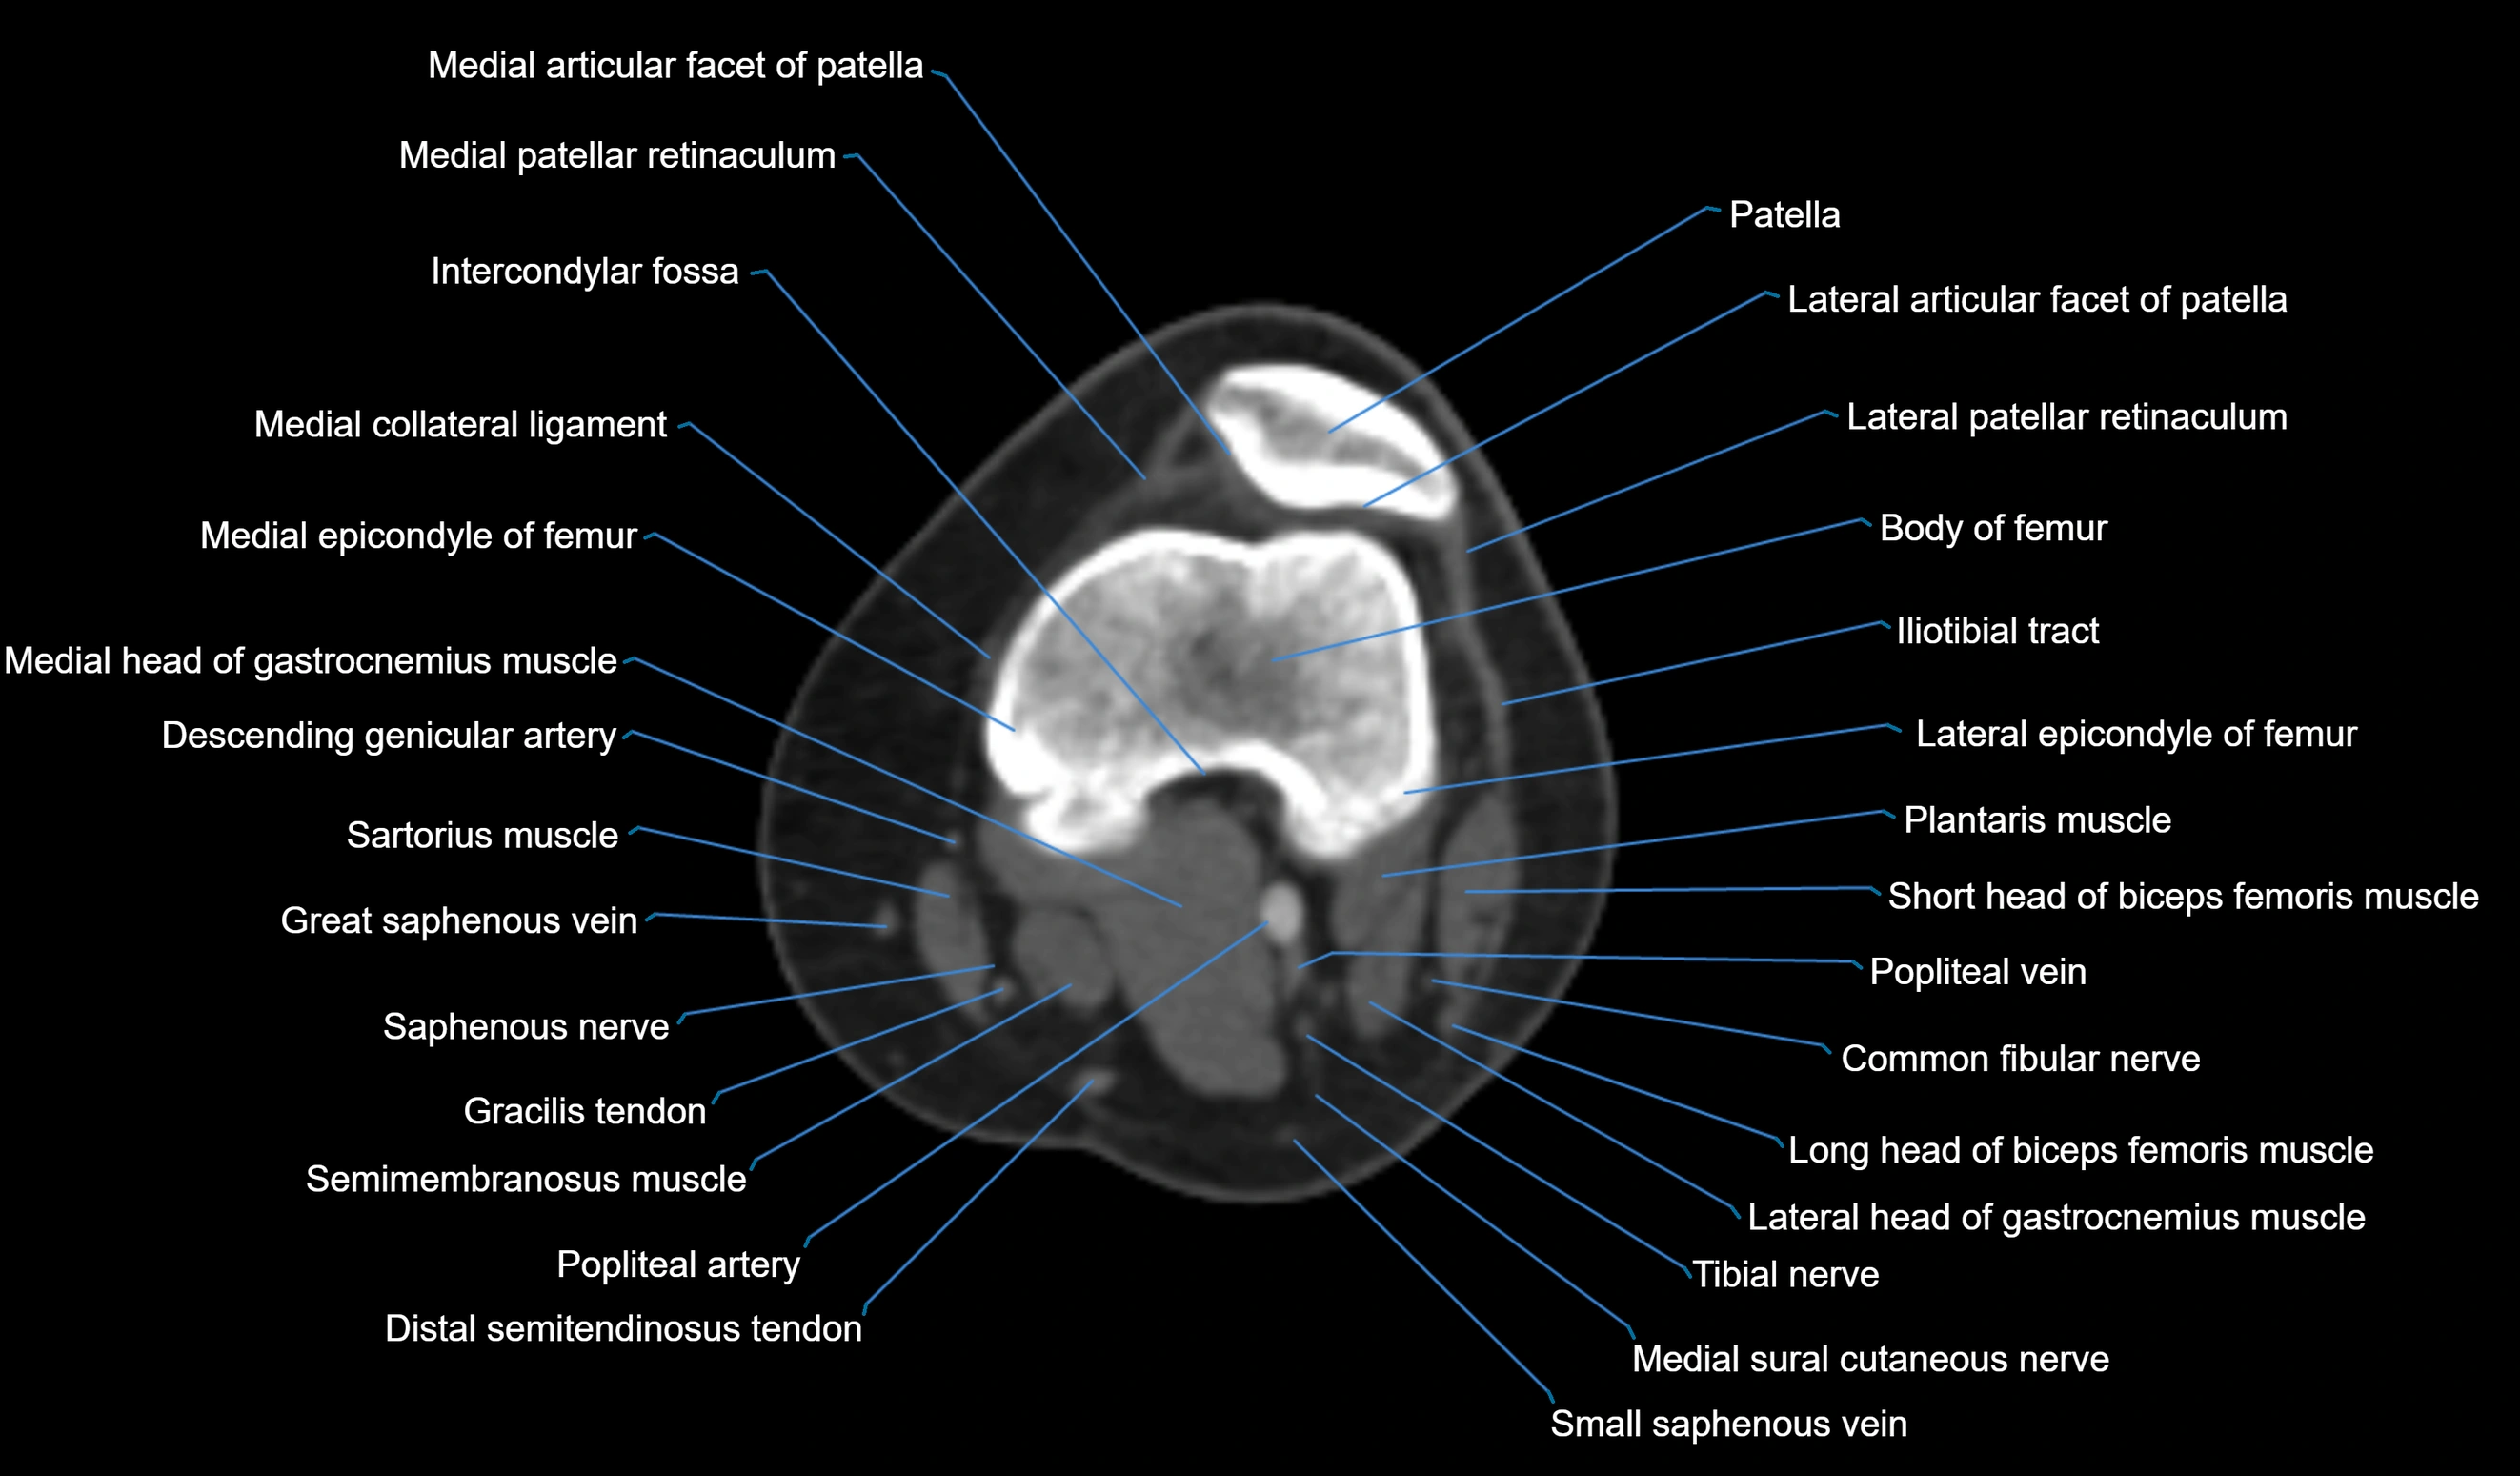

- Intercondylar fossa

- Lateral articular facet of patella

- Lateral epicondyle of femur

- Lateral head of gastrocnemius muscle

- Lateral patellar retinaculum

- Medial articular facet of patella

- Medial collateral ligament

- Medial epicondyle of femur

- Medial head of gastrocnemius muscle

- Medial patellar retinaculum

- Patella

- Popliteal artery

- Popliteal vein

- Saphenous nerve

- Sartorius muscle

- Semimembranosus muscle

- Small saphenous vein

- Tibial nerve